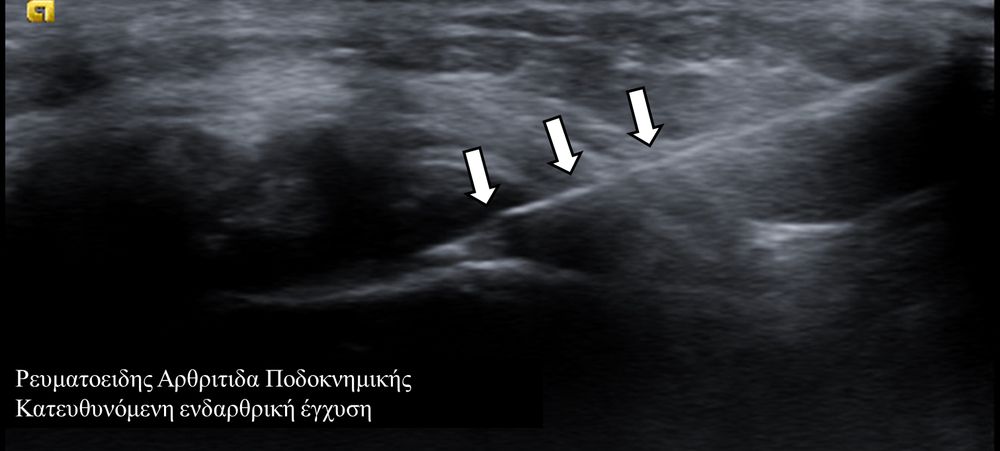

Υπό συνεχή υπερηχογραφική παρακολούθηση είναι δυνατόν να πραγματοποιηθούν κατευθυνόμενες εγχύσεις σε ορθοπαιδικές και ρευματολογικές παθήσεις. Αρχικά εντοπίζεται η παθολογική περιοχή και στη συνέχεια εξετάζεται η βέλτιστη οδός προσπέλασης. Ακολούθως γίνεται υπό άμεση και συνεχή υπερηχογραφική παρακολούθηση οι απαραίτητοι χειρισμοί και έγχυση φαρμάκων ακριβώς στη θέση της βλάβης.

Οι διαγνωστικές-θεραπευτικές εγχύσεις είναι δυνατόν να γίνουν σε μια πλειάδα μυοσκελετικών-ρευματολογικών παθήσεων όπως:

- ενδοαρθρικά(πχ οστεοαρθρίτιδα)